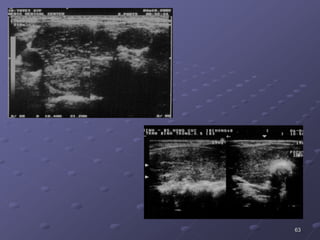

HASHIMOTO

63

64

Cöôøng

gia'p/ vieâm

giap